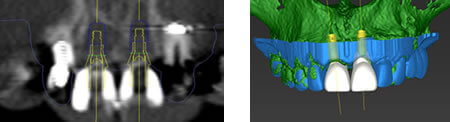

口腔内・全身状況を総合的に診断し、難症例でもインプラント手術を安全・正確に行うために、術前にPCでシミュレーションするガイドシステムを採用しております。

専用シミュレーションソフトで位置や種類の決定

専用のシミュレーションソフトでインプラントを植える位置や種類を決定します。

シミュレーションを行った位置にそのまま植えるためにより、安全で精密なガイデッドサージェリーを行うこともできます。

コンピュータガイデッドサージェリーとは、専用のソフトウェアを用いて、コンピュータ上でインプラント治療を計画した後、手術用のガイドを作製し、ガイドを用いてインプラント手術を行うことです。

これにより、計画通りの位置にインプラントを埋入することができ、より安全で正確な治療を行うことができます。